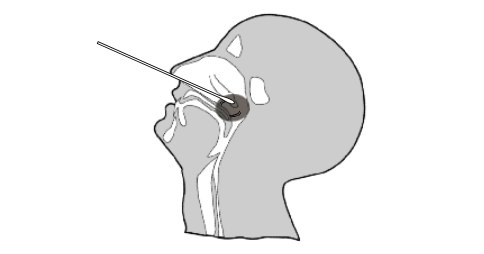

Nasopharyngeal Swab Specimen Collection

1. Insert a sterile swab into the nostril of the patient, reaching the surface of the posterior nasopharynx.

2. Swab over the surface of the posterior nasopharynx.

3. Withdraw the sterile swab from the nasal cavity.